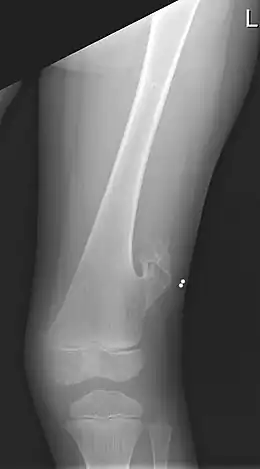

Radiographie du fémur gauche d'un garçon de 5 ans présentant une exostose latérale, juste au-dessus du genou.